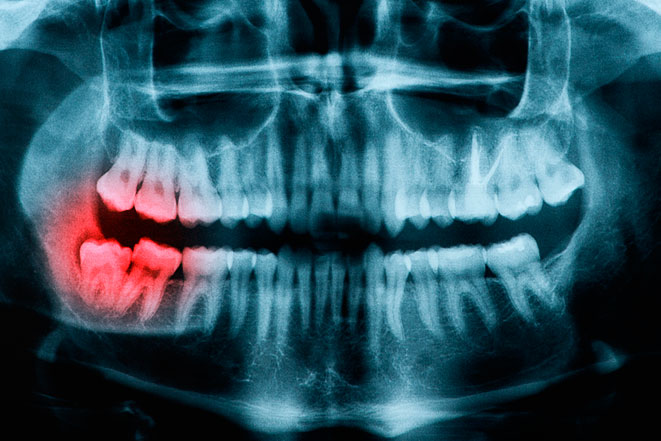

Последствия ретенции зубов

В этой статье мы расскажем про последствия ретенции зубов для человека.

Ретинированный зуб. Задержка прорезывания

В этой статье мы расскажем что такое ретинированный зуб.